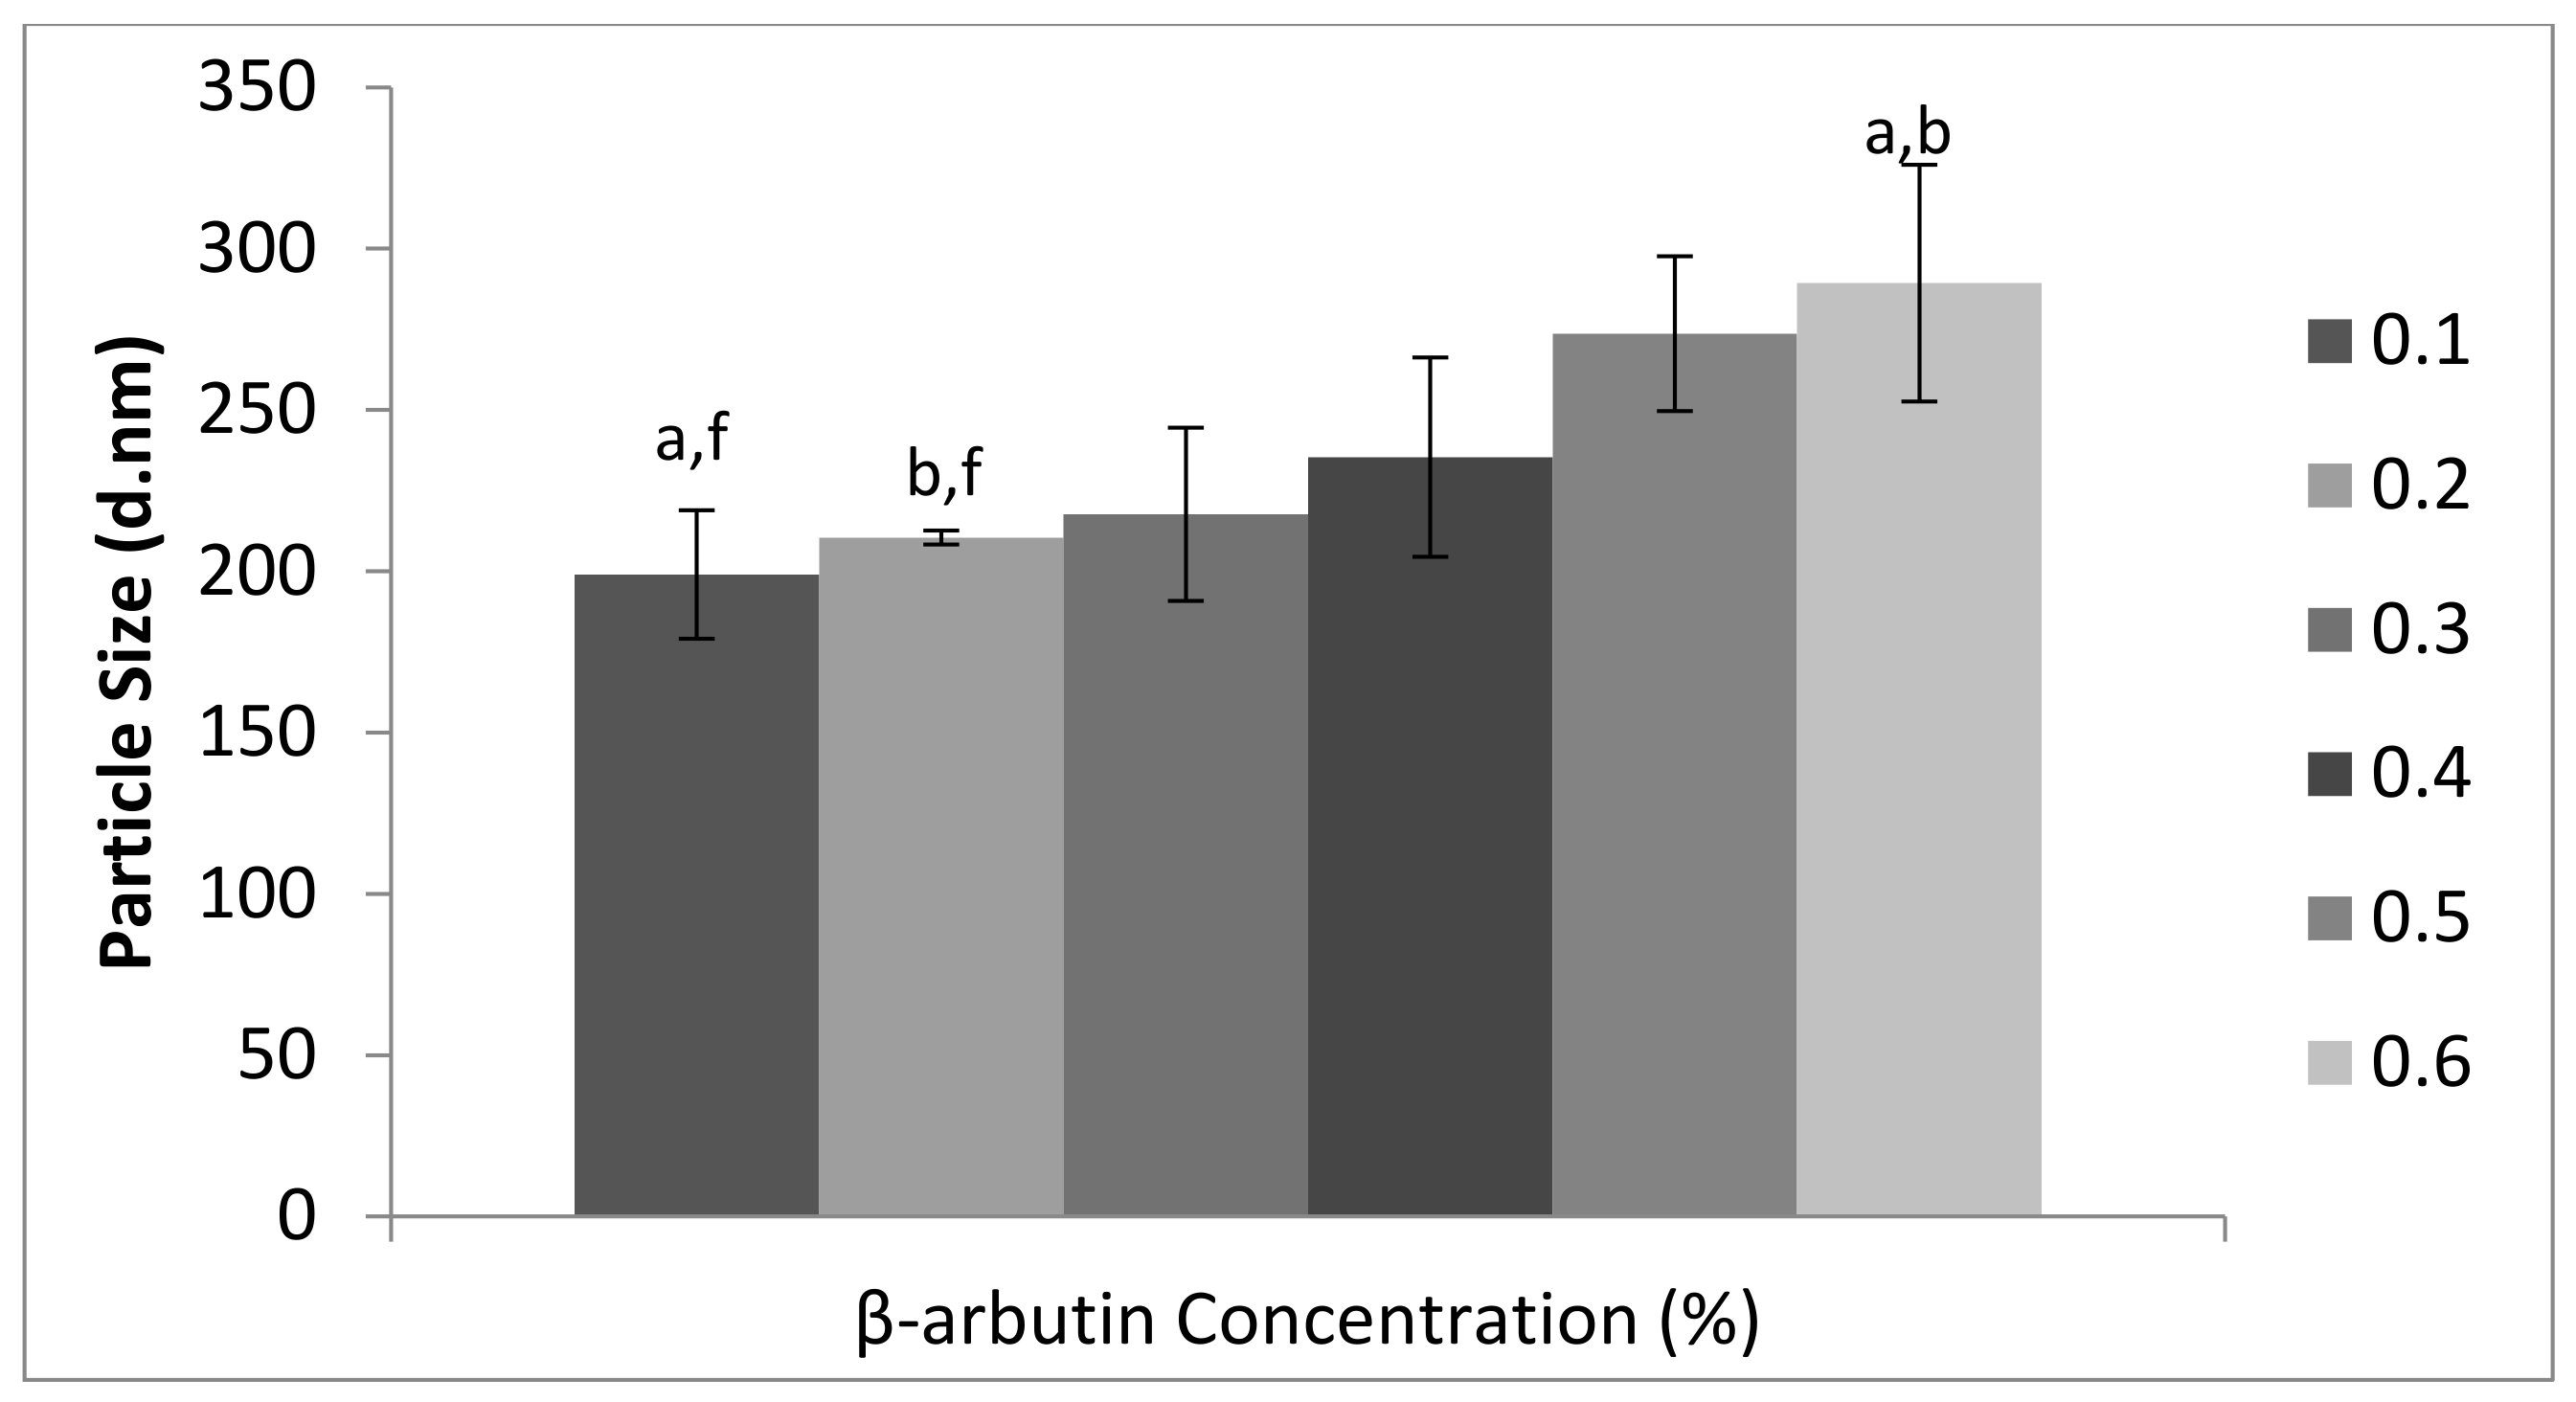

3.1. Physicochemical Characterization β-Arbutin CSNPs

2.3. Evaluation of Polydispersity Index, Particle Size, and Zeta Potential